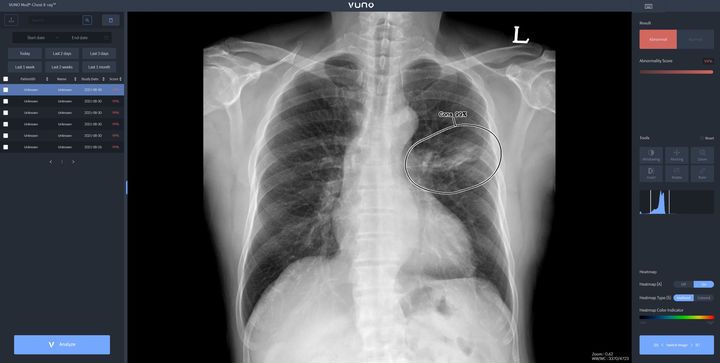

[서울=뉴시스] 22일 의료 인공지능(AI) 기업 뷰노는 아랍에미리트(UAE) 국군 병원인 자이드 군 병원(Zayed Military Hospital)에 인공지능 기반 엑스레이(X-ray) 판독 보조 솔루션을 공급했다고 밝혔다. (사진=뷰노 제공) 2024.04.22 [email protected] *재판매 및 DB 금지

자이드 군 병원에 도입된 솔루션은 이동형 엑스레이 장비에 뷰노의 AI 기반 흉부 엑스레이 판독 보조 솔루션 뷰노메드 체스트 엑스레이를 탑재한 패키지 제품이다. 별도의 차폐 시설 없이 다양한 상황에서도 쉽게 환자의 흉부 엑스레이 촬영을 할 수 있는 이동형 장비에 인공지능을 연동해 수 초 이내에 판독 결과를 확인할 수 있다.

뷰노메드 체스트 엑스레이는 흉부 엑스레이 영상에서 결절, 경화, 간질성 음영, 흉수, 기흉 등 주요 이상소견을 높은 정확도로 탐지하는 인공지능 솔루션이다.